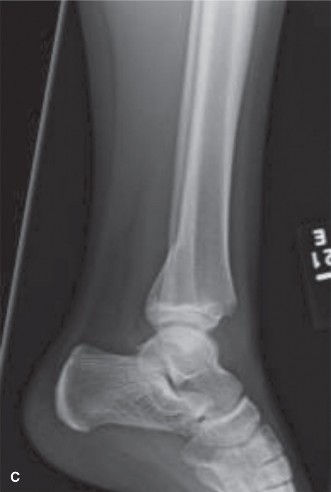

Upon completion of the secondary survey, portable radiographs are obtained in the trauma bay to assess the fracture pattern and the adequacy of the applied traction.

The initial anteroposterior (AP) and lateral radiographs of the right femur demonstrate a complete, displaced, length-stable transverse fracture of the middle third of the femoral diaphysis. There is minimal comminution. The traction splint has effectively restored length, though there remains slight apex-lateral and apex-anterior angulation.

Crucially, dedicated AP and lateral views of the right hip and right knee are obtained. The femoral neck is intact, with no evidence of a basicervical or transcervical fracture—a classic "missed injury" in the setting of high-energy femoral shaft fractures. The distal femoral physis is open and symmetric, with no widening or displacement to suggest a concurrent Salter-Harris injury.